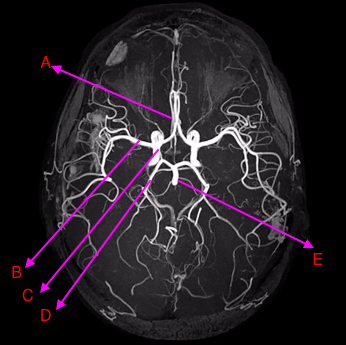

draw the circle of willis xxx

Label A-C

A: anterior cerebral artery

B: middle cererbral artery

C: internal carotid artery